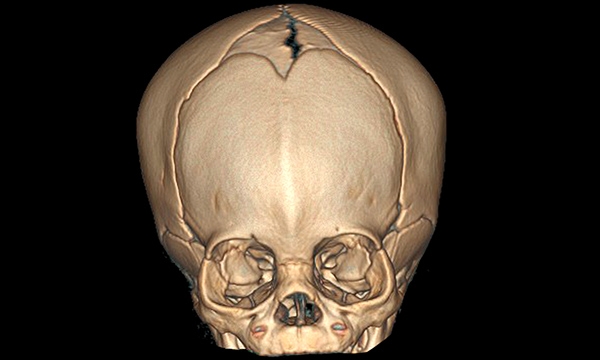

Pfeiffer syndrome is a genetic condition thought to occur once in every 100,000 people